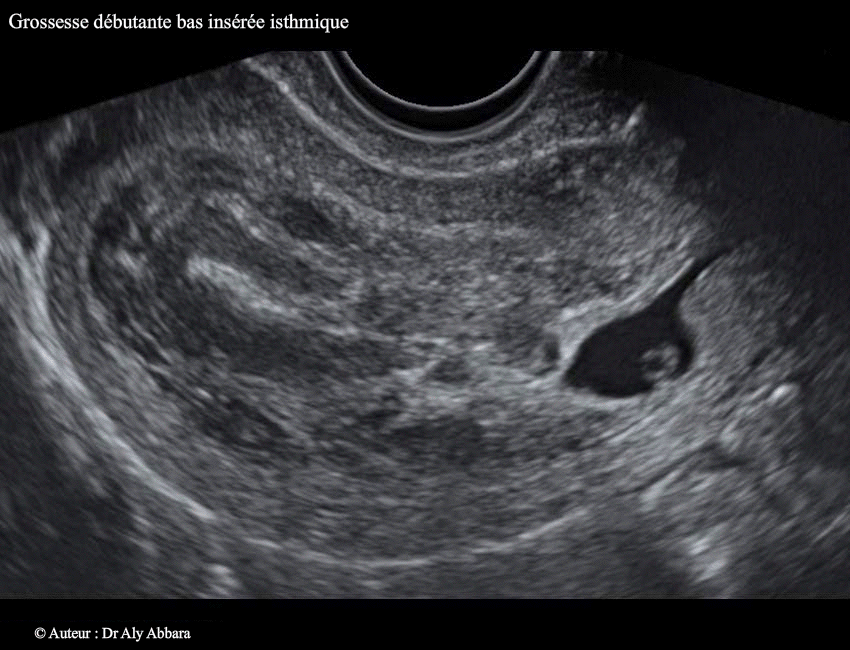

• Images échographiques montrant l'évolution spontanée d'une grossesse débutante à insertion basse, dans la zone isthmique de la cavité utérine (grossesse isthmique utérine).

• Biologiquement : au moment du premier examen échographique (J/0) le dosage de β-hCG plasmatique était égal à 10 400 UI/l.

• Cliniquement : 2ème geste avec antécédent d'accouchement normal.

6 SA ; des légères douleurs pelviennes associées à des spottings intermittents.

• Échographiquement on peut observer à travers les images ci-dessus que le sac gestationnel qui s'est implanté dans la région isthmique de la cavité utérine continue à évoluer lors du contrôle, à 2 jours et à 4 jours après l'examen initial, avec l'apparition d'une image embryonnaire munie d'une activité cardiaque et mesurant, à J4, 2,3 mm.

Le sac gestationnel était partiellement décollé au niveau de son pôle supérieur dès l'examen initial. Ce décollement s'élargissait à J2 et à J4 ; il est à l'origine (dès l'examen initial) de la formation d'une hématométrie qui s'aggravait au cours du développement de la grossesse (36 ml à J4 et 47 ml à J6) ; deux éléments participaient à sa formation : le décollement progressif du sac gestationnel et l'effet de bouchon exércé par ce sac sur le canal cervical en l'obstruant au niveau de son orifice interne.